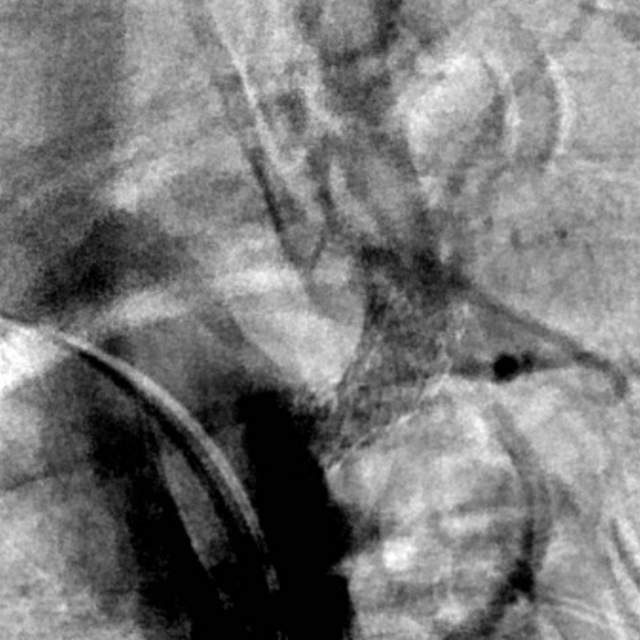

最近,儿子带老人家过来复查,检查发现右侧椎动脉起始部的狭窄越来越重,和9个月前相比,简直判若两人(管),左侧椎动脉又先天发育不好……,看来保守治疗吃药不太行,还得需要外科干预

和家属商量后,我们采用全球首款椎动脉专用药物洗脱支架(Maurora)成功精准切线位植入,消除了这个“卡脖子”的狭窄……